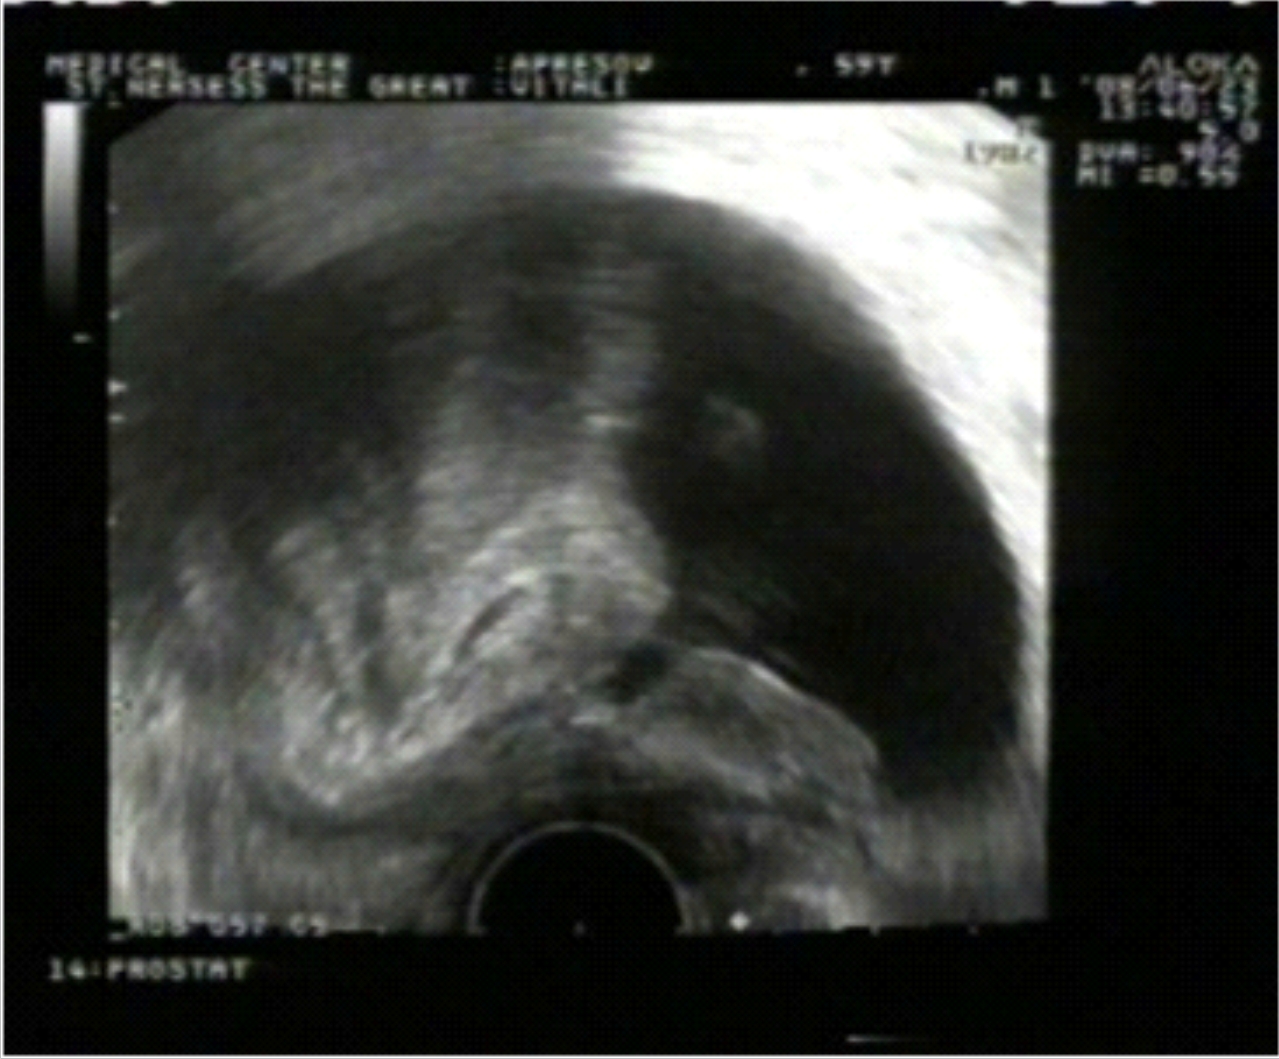

Վերջում ցանկանում ենք ներկայացնել մեր հետազոտությունների ժամանակ տրանսռեկտալ ուլտրաձայնային հետազոտության միջոցով հայտնաբերված տեղային ռեցիդիվի դեպք, որը դիտվել է գորշ սանդղակ (նկ. 1) և էներգետիկ դոպպլեր ռեժիմներով (նկ. 2): Սկանավորումը կատարվել է արմատական պրոստատէկտոմիայից 6 ամիս անց: Միզապարկի վզիկի աջ հատվածում` բերանակցման զոնային հարակից երևում է հիպերվասկուլյար օջախ, որը տրանսռեկտալ թիրախային բիոպսիայով ախտորոշվել է շագանակագեղձի ադենոկարցինոմա (Գլիսոն 3+4=7 բալ):

Նկ. 1 Նկ. 2